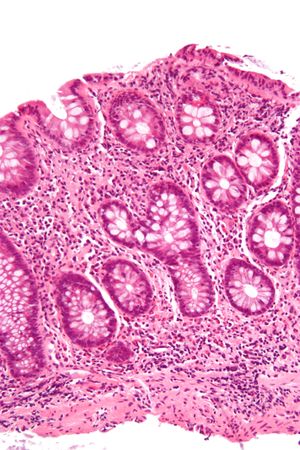

| ميكروگراف يـُظهـِر cryptitis, a ارتباط مجهري لالتهاب القولون. H&E stain. | |